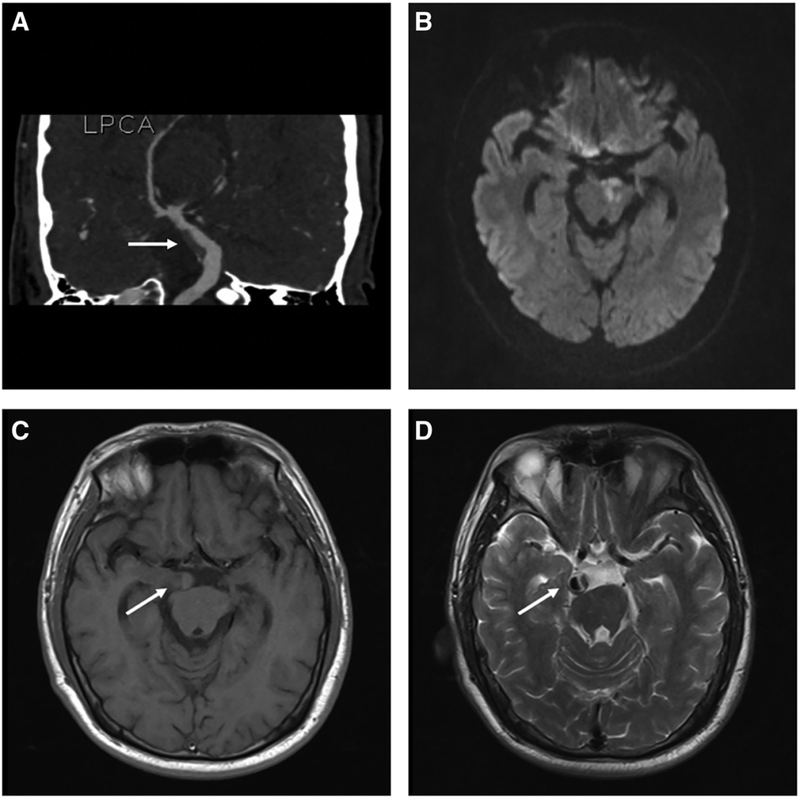

Stroke:椎基底動(dòng)脈擴(kuò)張延長癥的血栓形成過程腦血管病及重癥文獻(xiàn)導(dǎo)讀?2024-01-1506:00?29歲,男性。因急性構(gòu)音障礙和右側(cè)偏癱11小時(shí)就診。CT成像顯示基底動(dòng)脈擴(kuò)張延長。CTA證實(shí)左側(cè)椎動(dòng)脈和基底動(dòng)脈擴(kuò)張延長,基底動(dòng)脈附壁血栓。MRI顯示急性左側(cè)腦橋梗死、基底動(dòng)脈擴(kuò)張和附壁血栓(圖1)。圖1.椎基底動(dòng)脈擴(kuò)張延長癥的附壁血栓。A、冠狀位CTA顯示基底動(dòng)脈擴(kuò)張,伴附壁血栓(白色箭頭)。B、軸位DWI顯示橋腦彌散抑制。C和D,T1MR顯示附壁血栓呈等-高信號(hào)(iso-hyperintensity),提示由新舊血栓混合而成,T2加權(quán)成像顯示等信號(hào)(iso-intense)血栓,管腔高信號(hào),伴有腦干和右海馬受壓(白色箭頭):給予靜脈輸液、替羅非班和強(qiáng)化阿托伐他汀治療。入院12小時(shí)后,患者突然意識(shí)喪失,伴有抽搐和瞳孔不等大。立即CTA顯示急性基底動(dòng)脈閉塞。緊急血栓切除術(shù),并移除一個(gè)大的附壁血栓(圖2)。圖2.患者病情惡化后DSA。A、DSA顯示嚴(yán)重的基底動(dòng)脈擴(kuò)張延長伴急性基底動(dòng)脈閉塞(白色箭頭)。B、取栓后DSA顯示基底動(dòng)脈和雙側(cè)大腦后動(dòng)脈的再通,mTICI評(píng)分為3:20天后,轉(zhuǎn)康復(fù)機(jī)構(gòu),mRS評(píng)分為5,在3個(gè)月的隨訪中預(yù)后不佳。椎基底動(dòng)脈擴(kuò)張延長是一種進(jìn)行性復(fù)雜的腦動(dòng)脈疾病,其特征是椎基底動(dòng)脈異常延長、擴(kuò)張和扭曲,發(fā)病機(jī)制不明。擴(kuò)張延長椎基底動(dòng)脈的血栓可能由新鮮和陳舊成分組成,血栓可以在數(shù)小時(shí)內(nèi)加重,需要更積極的治療。急性血栓形成可以通過靜脈溶栓治療,閉塞性血栓可以采取取栓治療,但療效尚不確定。文獻(xiàn)出處:Stroke.2023Dec;54(12):e494-e495.doi:10.1161/STROKEAHA.123.044834.Epub2023Oct5.AcuteBasilarArteryOcclusionInducedbyRapidlyProgressiveThrombosisinVertebrobasilarDolichoecta